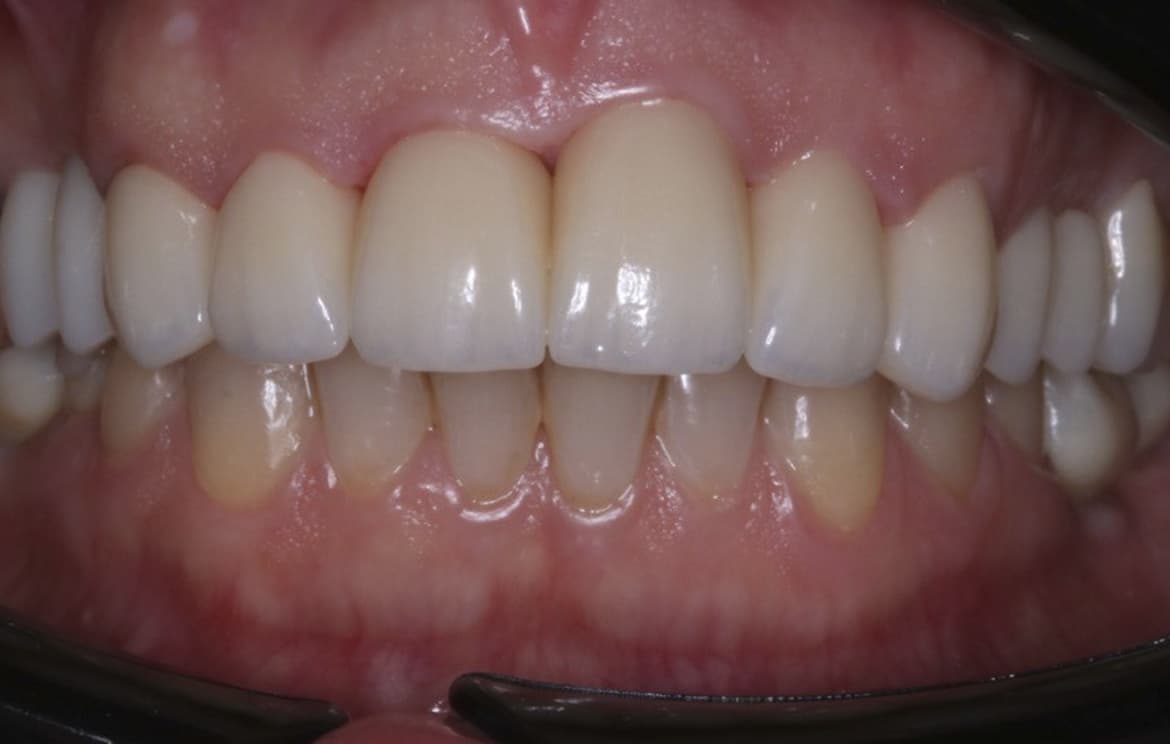

Наши работы